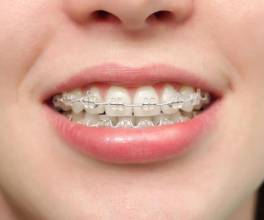

До лечения

Подросток 12 лет. Глубокий прикус, выраженный дефицит места для верхних клыков и премоляров внизу.Смещение средней линии зубов. Жалобы – «не прорезываются зубы»